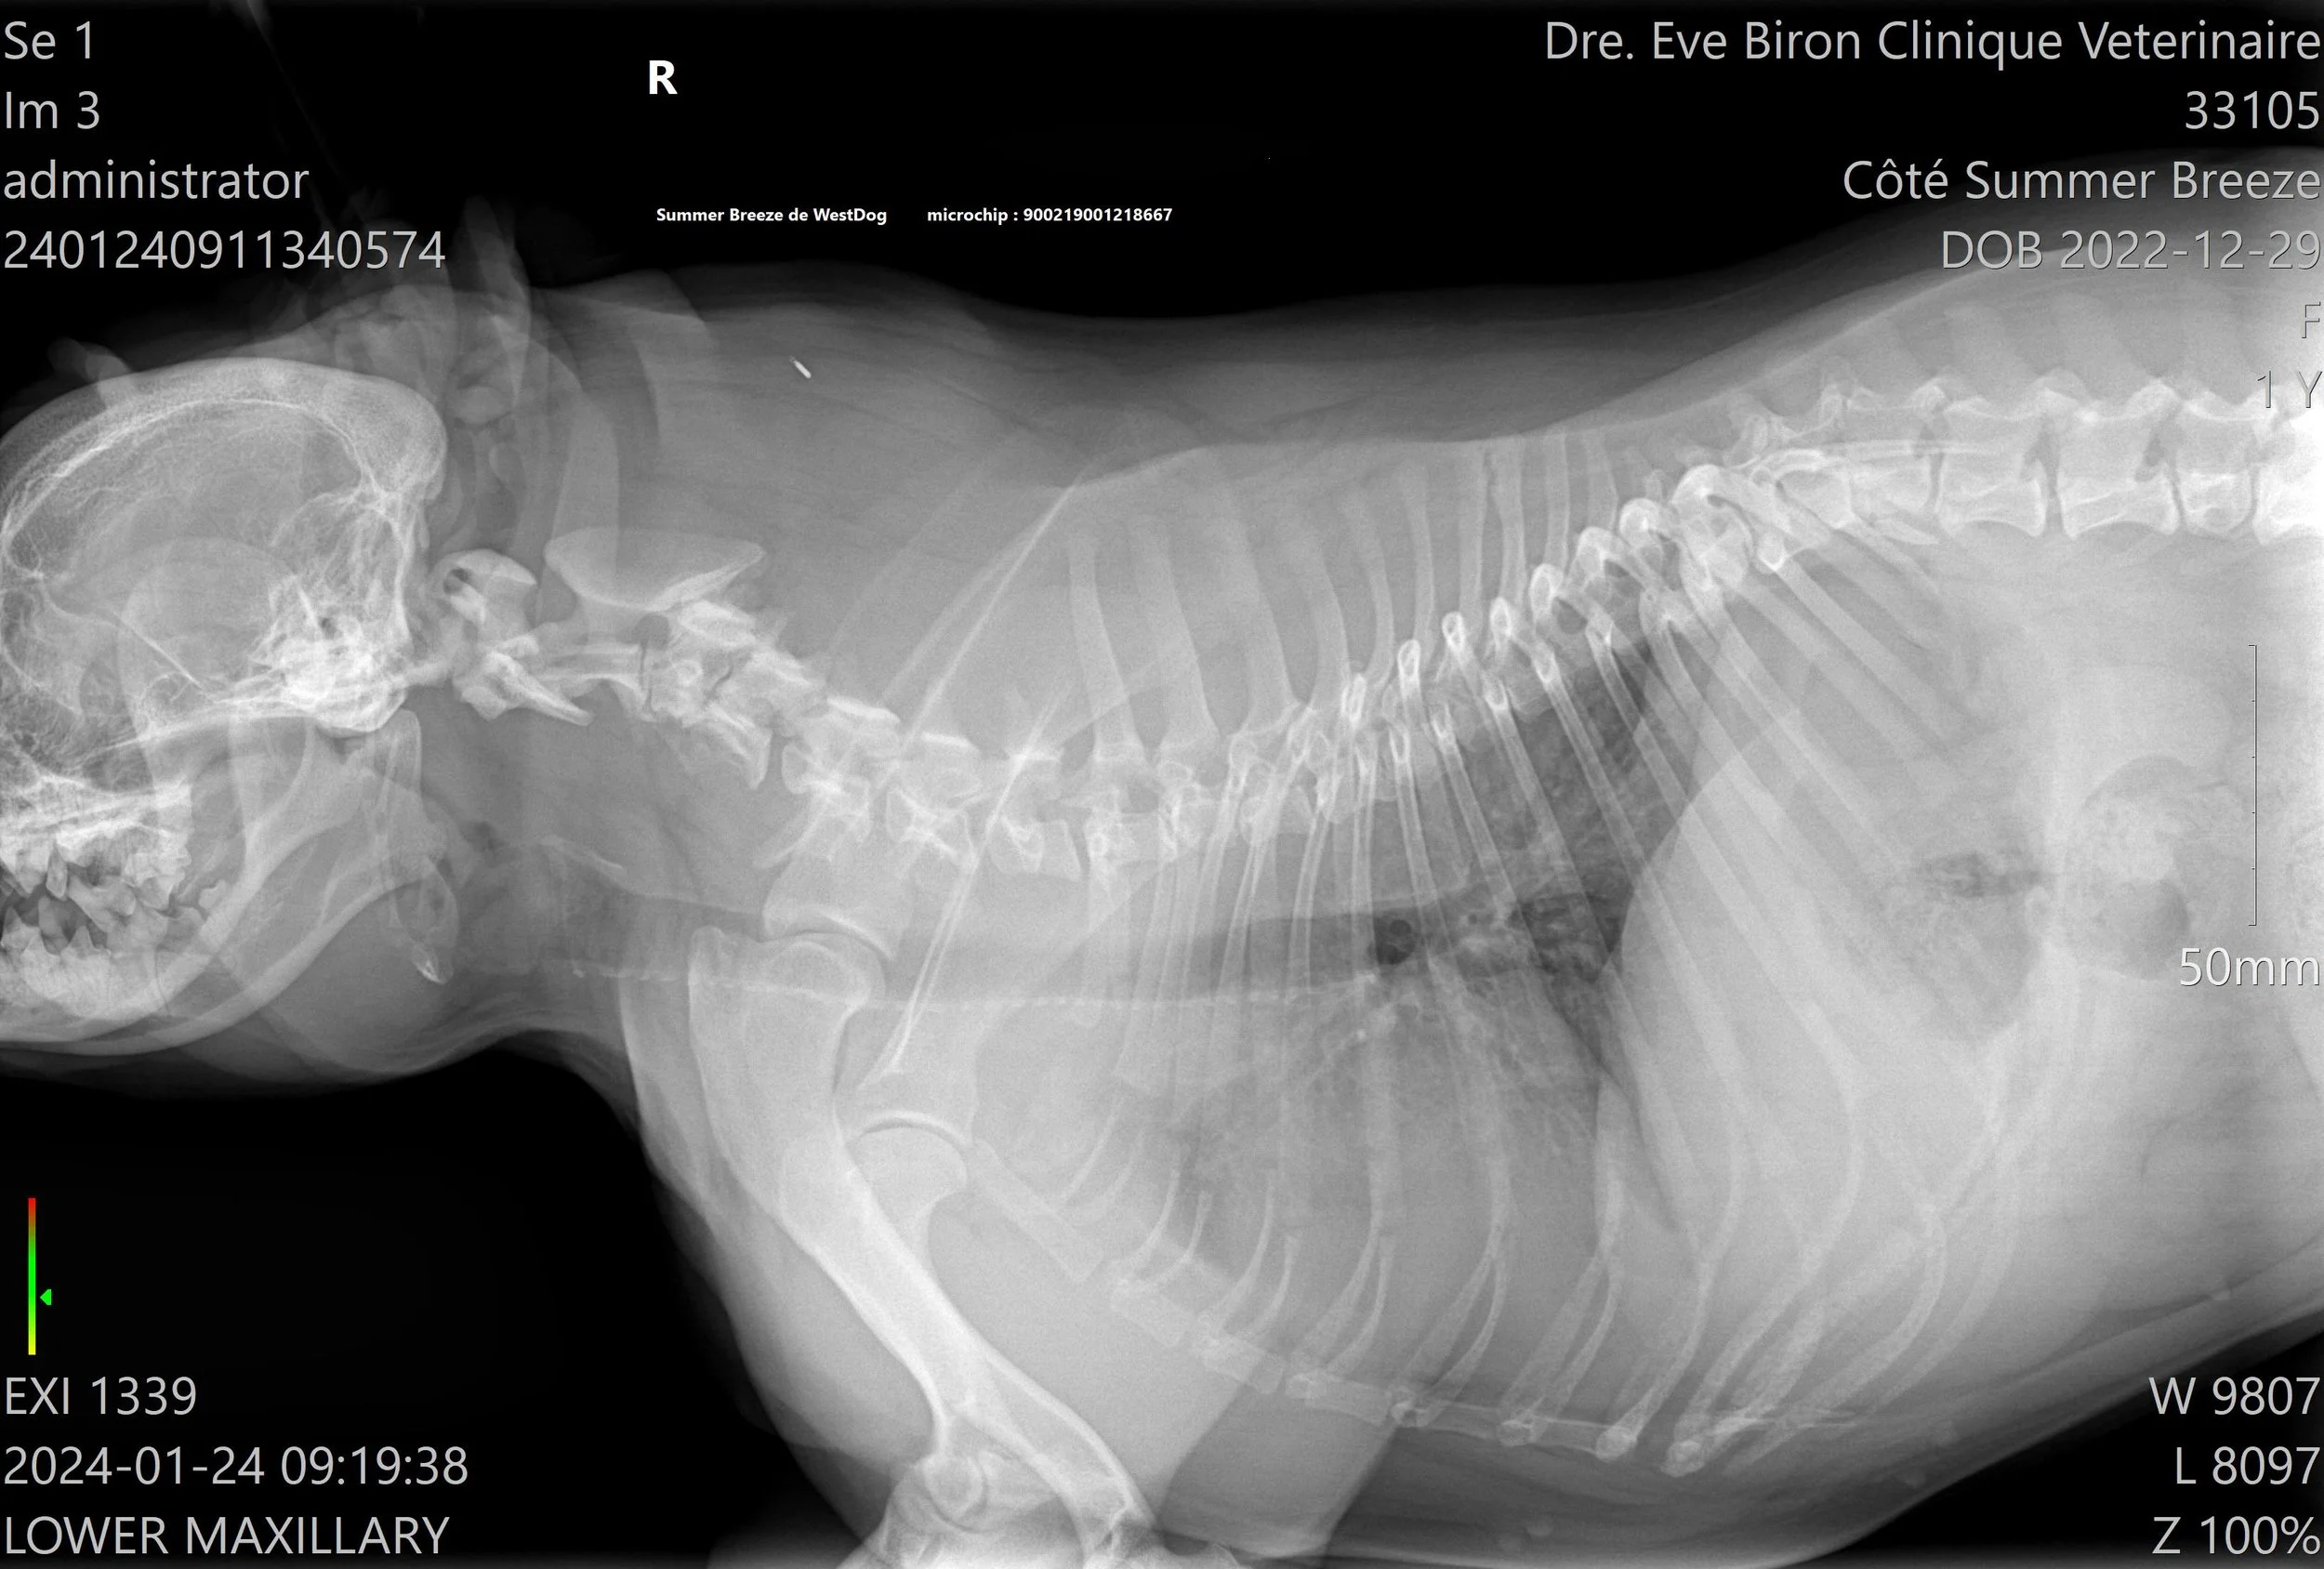

L’OFA recommande de faire des tests de biomécanique du chien: Dysplasie de la hanche, Luxation des rotules, Examen oculaire, évaluation cardiaque, Coude, Thyroïdite, et Trachée.

Tous ces tests doivent être fait par des vétérinaires et certains laboratoires accrédités. La vérification de l’enregistrement original du chien AKC et de l’identification par micropuce ou tatou est obligatoire pour que le vétérinaire puisse signer et envoyer les radiographies de façon électronique, de la clinique vétérinaire à L’OFA et ainsi éviter les fraudes.

L'OFA est un organisme à but non lucratif situé aux États-Unis qui permet de publier les résultats des tests fait par les vétérinaires et les laboratoires accrédités. 3 vétérinaires indépendants spécialisés, évaluent les radiographies et leurs donnent des “quotes”. C’est une excellente façon de prouver qu’un éleveur a le souci de dépister des problèmes potentiels sur les animaux qu’il prévoit reproduire, et de montrer au public les résultats des épreuves complétées. Comme la majorité des gens ne sont pas spécialisés en lecture de radiographies, les notes données par L’OFA sont impartiales et permettent d’avoir une vraie vue d’ensemble.

Pour la méthode traditionnelle, celle de l’OFA (Orthopedic Foundation for Animals), une seule radiographie est prise. Avec la méthode PennHIP, ce sont trois prises de vues qui sont réalisées. Elles permettent au vétérinaire de détecter la présence d’arthrose dans l’articulation et de calculer le degré de relâchement (s’il y en a un). Le PennHIP peut être effectué à partir de l’âge de 16 semaines, ce qui en fait une méthode de dépistage précoce. La dysplasie de la hanche est une maladie génétique qui affecte les chiots dès leur plus jeune âge.